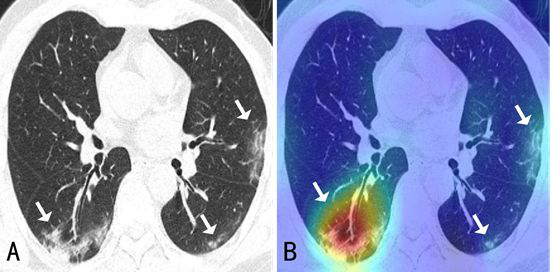

Hospital uses Fudan’s AI system to locate lesions in lung